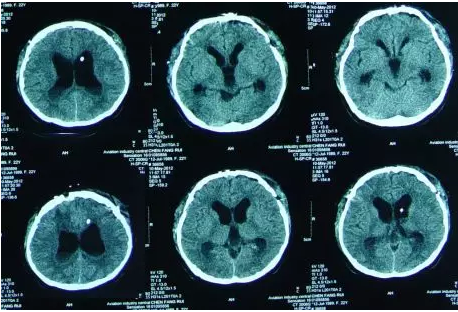

内镜造瘘术后第4天即脑室外引流拔除后第2天即2012年5月2日,腰穿提示颅内压高达400mmH20,查头CT:三脑室又扩大(图-4),查头MRI:小脑扁桃体轻微下疝(图-5),医生考虑三脑室再次扩大跟小脑扁桃体下疝有关,给予腰大池引流相关治疗。

图-4:2012年5月2日头CT

图-5:2012年5月2日头MRI